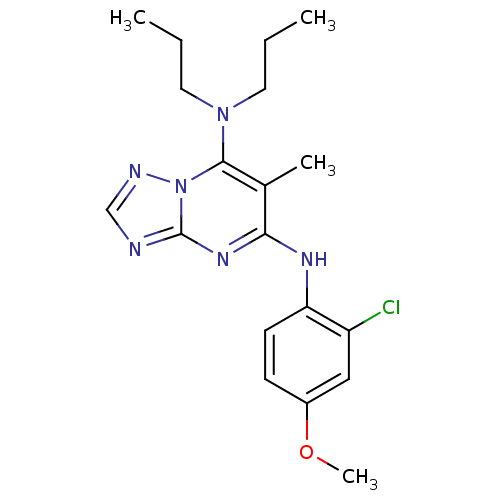

TargetCorticotropin-releasing factor receptor 1(Homo sapiens (Human))

Dupont Pharmaceuticals

Curated by ChEMBL

Dupont Pharmaceuticals

Curated by ChEMBL

Affinity DataEC50: 0.600nMAssay Description:Antagonist activity at human CRF1 receptor expressed in CHO-K1 cells assessed as CRF-stimulated cAMP accumulation by enzyme immunoassayMore data for this Ligand-Target Pair

TargetCorticotropin-releasing factor receptor 1(Homo sapiens (Human))

Dupont Pharmaceuticals

Curated by ChEMBL

Dupont Pharmaceuticals

Curated by ChEMBL

Affinity DataEC50: 0.700nMAssay Description:Antagonist activity at human CRF1 receptor expressed in CHO-K1 cells assessed as inhibition of CRF-induced cAMP accumulation after 15 mins by cAMP en...More data for this Ligand-Target Pair

TargetCorticotropin-releasing factor receptor 1(Homo sapiens (Human))

Dupont Pharmaceuticals

Curated by ChEMBL

Dupont Pharmaceuticals

Curated by ChEMBL

Affinity DataEC50: 0.700nMAssay Description:Antagonist activity at human CRF1 receptor expressed in CHO-K1 cells assessed as CRF-stimulated cAMP accumulation by enzyme immunoassayMore data for this Ligand-Target Pair

Affinity DataEC50: 0.700nMAssay Description:Antagonist activity at CRF-R1 in mouse AtT-20 cells assessed as inhibition of human CRF induced cAMP accumulation after 30 mins by radioimmunoassayMore data for this Ligand-Target Pair

Affinity DataEC50: 0.800nMAssay Description:Antagonist activity at CRF-R1 in mouse AtT-20 cells assessed as inhibition of human CRF induced cAMP accumulation after 30 mins by radioimmunoassayMore data for this Ligand-Target Pair